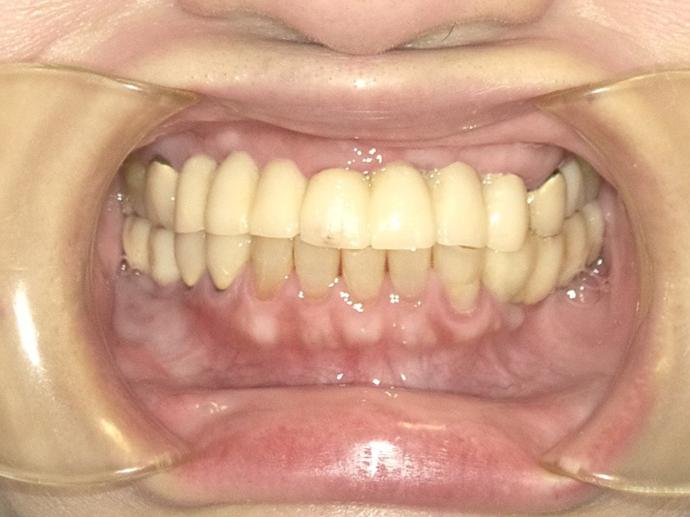

臨時假牙重建上下顎的垂直關係